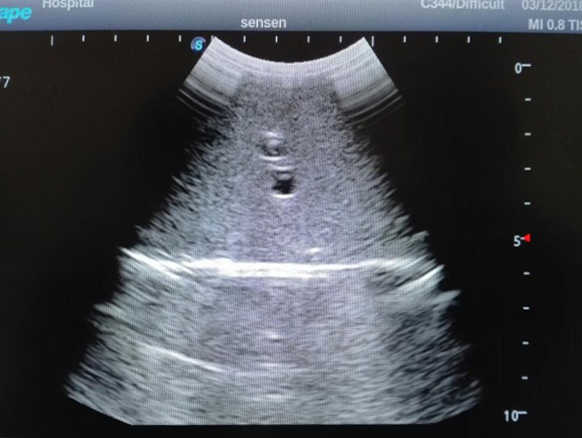

2)  High quality ultrasound image with clear structures like gallbladder, liver, intestines, arteries and veins etc.

4)  ltrasound gallbladder pathologies like cholecystitis, gallstone and polypoid degeneration

5)  Normal & pathological ultrasound live and intestine models inside